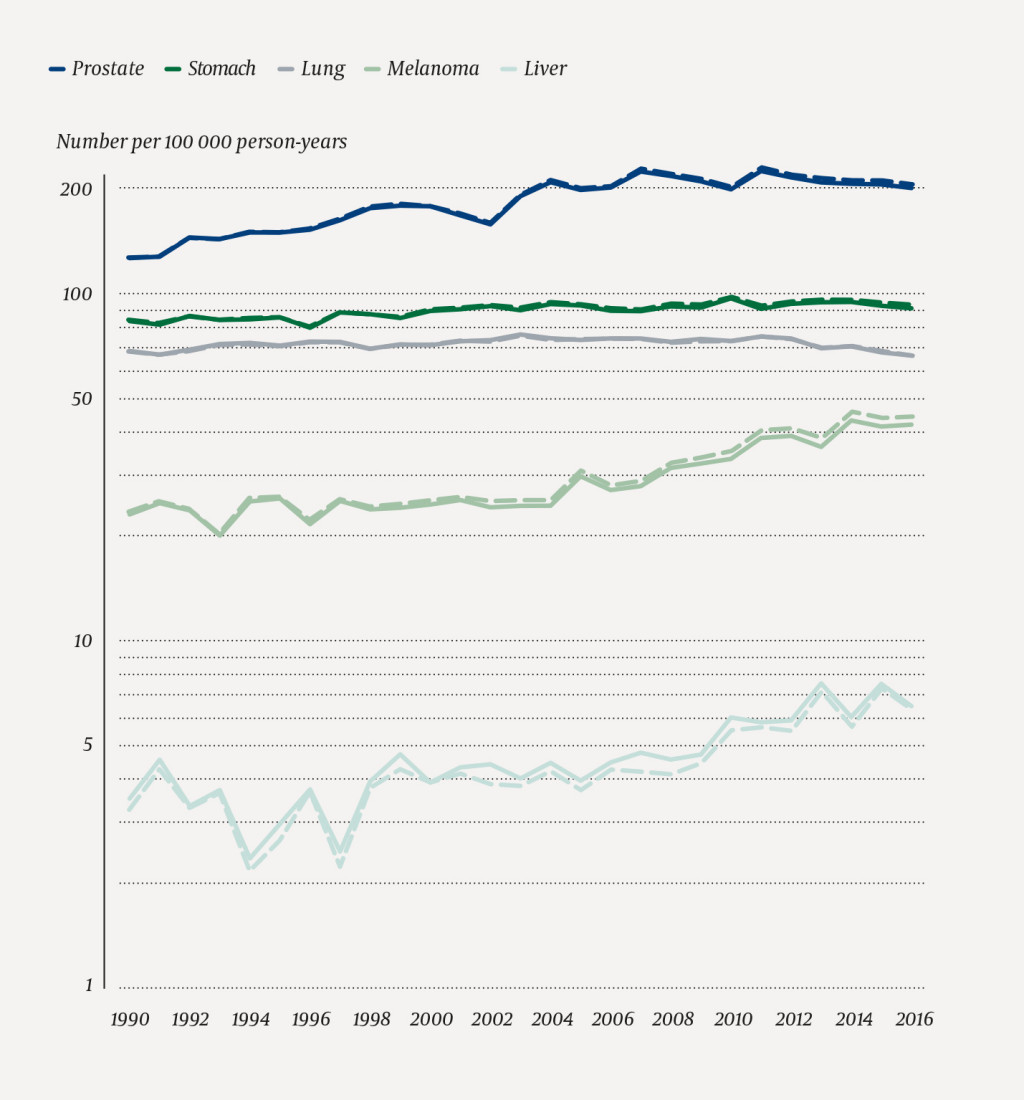

The age-standardised incidence rates for selected types of cancer, for the total population and the Norwegian-born, are shown in Figure 2 (men) and Figure 3 (women). The incidence rates for the Norwegian-born population were close to those of the total population for the major types of cancer: prostate, breast, stomach and lung cancer.

Figure 1 shows that the rates for the Norwegian-born portion of the population have remained somewhat higher than the national rates since the turn of the millennium. To quantify the differences in rates for the Norwegian-born and the total population we chose the last five-year period (2012–16) (Tables 1 and 2). For all types of cancer as a whole, the rates for the Norwegian-born were 2 % higher than the rates for the total population. Differences for the individual types of cancer varied from -6 % to +8 %. Melanoma and cancer of the cervix uteri were the types of cancer that showed the greatest positive percentage-wise differences between the rates. For melanoma, the rates for Norwegian-born men were 6 % higher than the national rates, while the rates for Norwegian-born women were 8 % higher. The rates for cancer of the cervix uteri were 8 % higher for Norwegian-born women when compared to the national rates. On the other hand, the rates for cancer of the liver among the Norwegian-born were 4 % lower for men and 3 % lower for women when compared to the rate in the total population. Cancer of the thyroid gland occurred 6 % less frequently among Norwegian-born women than in the total population. Since this is a relatively rare type of cancer, this corresponds to a difference of less than one case per 100 000 person-years (Tables 1 and 2).